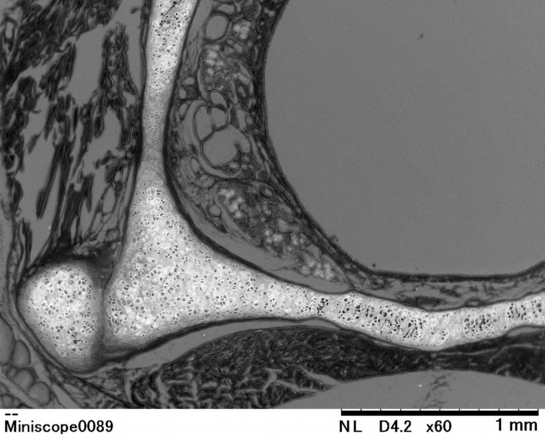

喉頭(ラット) Larynx ( rat )

【 厚さ30 µm パラフィン切片の低真空走査型電子顕微鏡画像 】

Low-voltage scanning electron microscopic image of 30 µm-thick paraffin section

喉頭がつぶれないように周囲を取り囲む硝子軟骨の構造が捉えられます

鉛染色のみ:軟骨組織は鉛染色に反応して白く観察されます